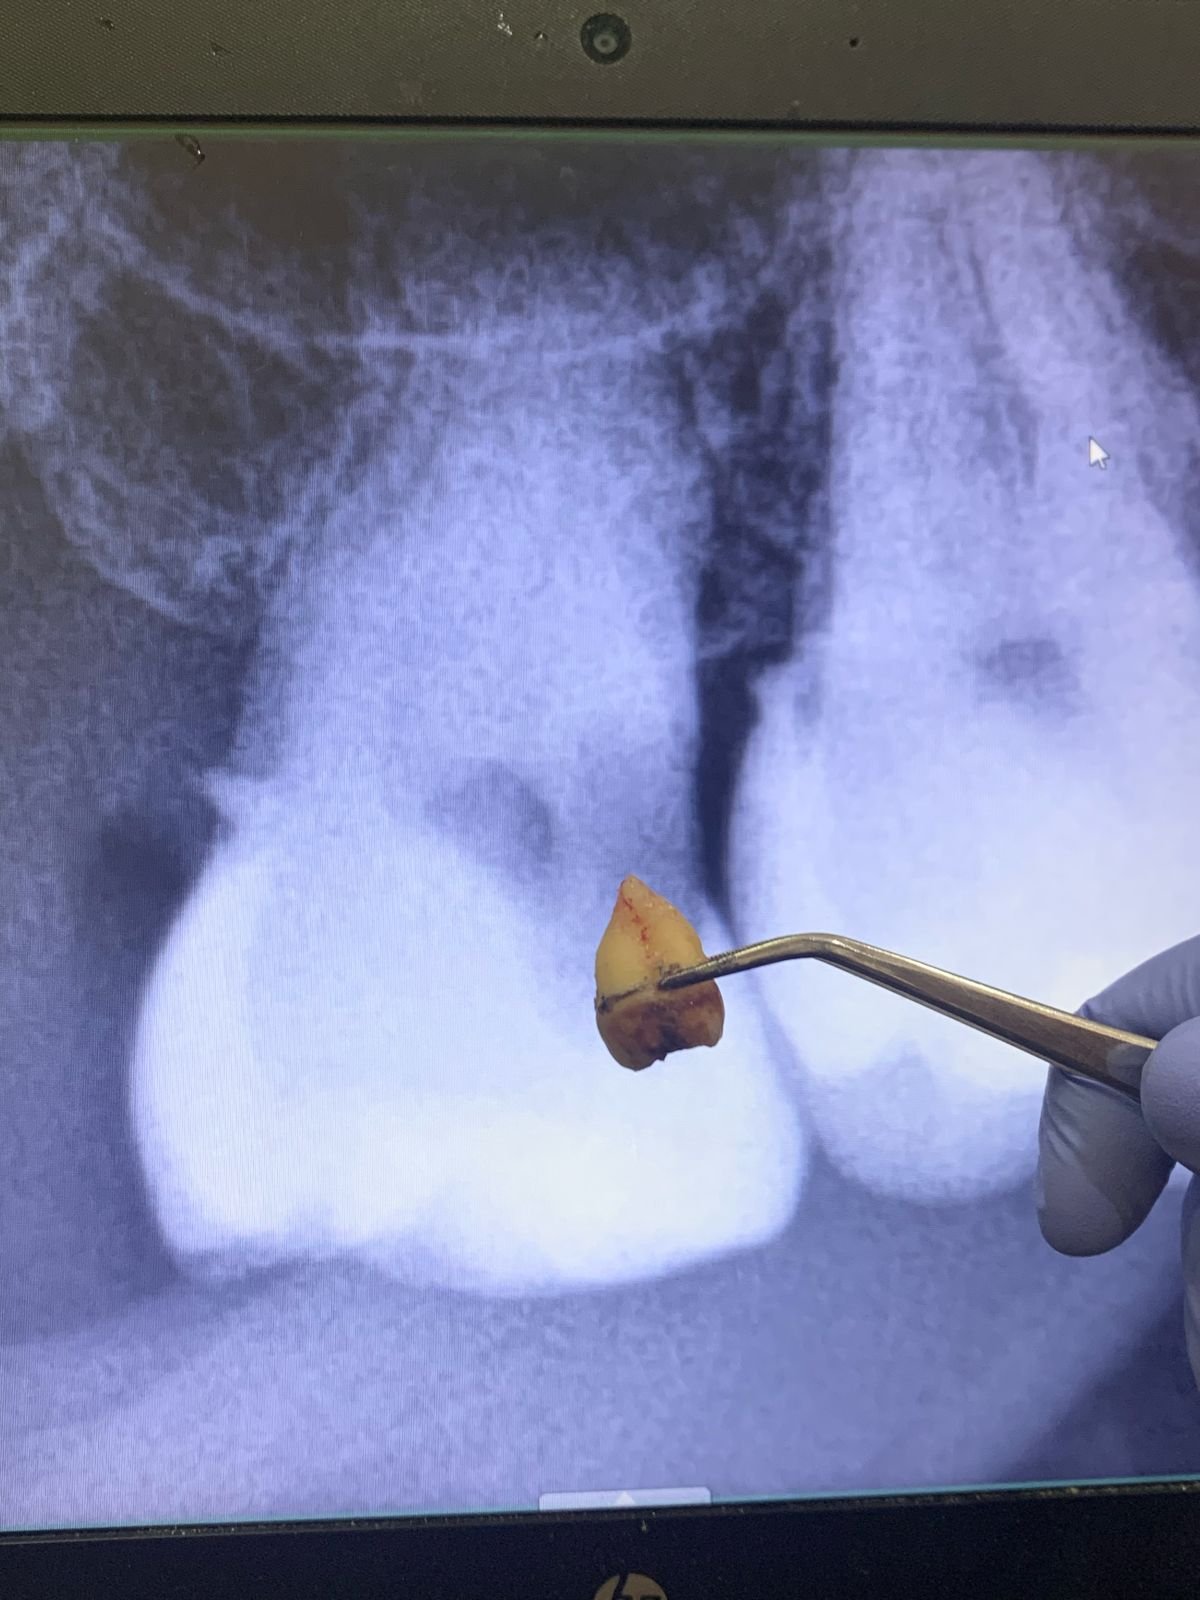

4. Pengangkatan gigi

Bila gigi sulit dicabut, dokter membaginya menjadi beberapa bagian lalu mengangkat potongan satu per satu.

After dari Cabut Gigi Bungsu